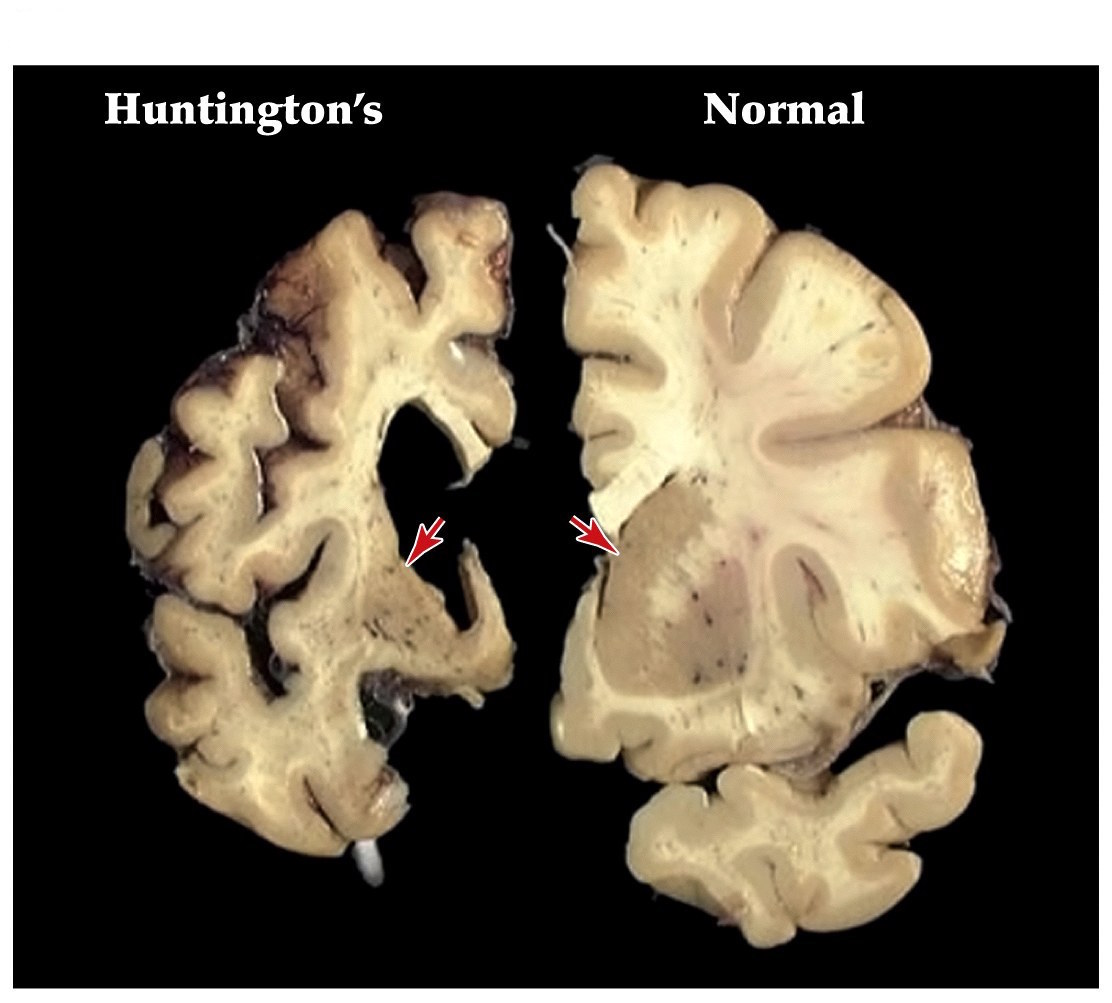

Huntington’s disease

- One of the most common inherited neurological diseases

- Progressive deterioration of the caudate and putamen that project to the GP externa (indirect pathway)

- Leads to a movement disorder consisting of rapid jerky motions with no clear purpose

Huntington’s disease

- Dominantly inherited– strikes around midlife

- Patients develop depression, mood swings, and abnormal movements (striatum)

- Caused by alterations in a single gene that encodes the huntingtin protein

- Huntingtin protein has an expansion of a CAG trinucleotide repeat, resulting in an extended polyglutamine repeat. Leads to aggregation of proteins and cell death

Hypokinetic and hyperkinetic disorders summary

- Parkinson's– hypokinetic disorder. More tonic inhibition of thalamus and decreased excitation of frontal cortex

- Huntington's– hyperkinetic disorder. Less tonic inhibition of thalamus and more excitation of frontal cortex